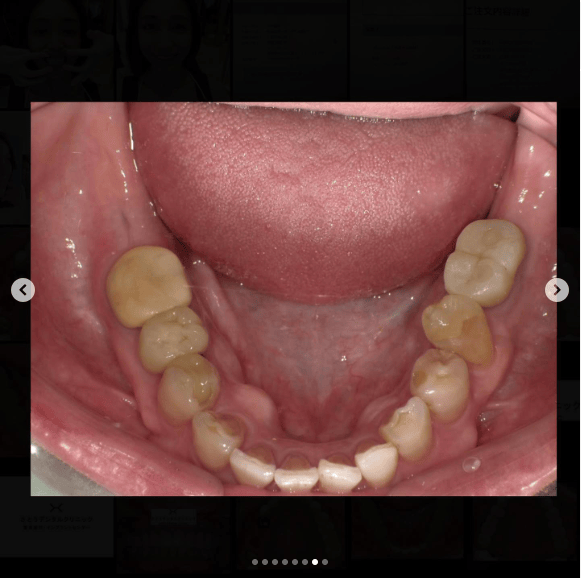

「今までほったらかしにしてきたけど、今回はちゃんと治したい」という主訴の患者様の治療です。

・できるだけ費用は抑えたい

・外見や将来の口腔内の健康に差が出るところは自由診療でやりたい

というご要望に沿う治療計画を立てて診療させていただきました。

最低限のセラミックとインプラントで機能的にも審美的にも回復することができました。